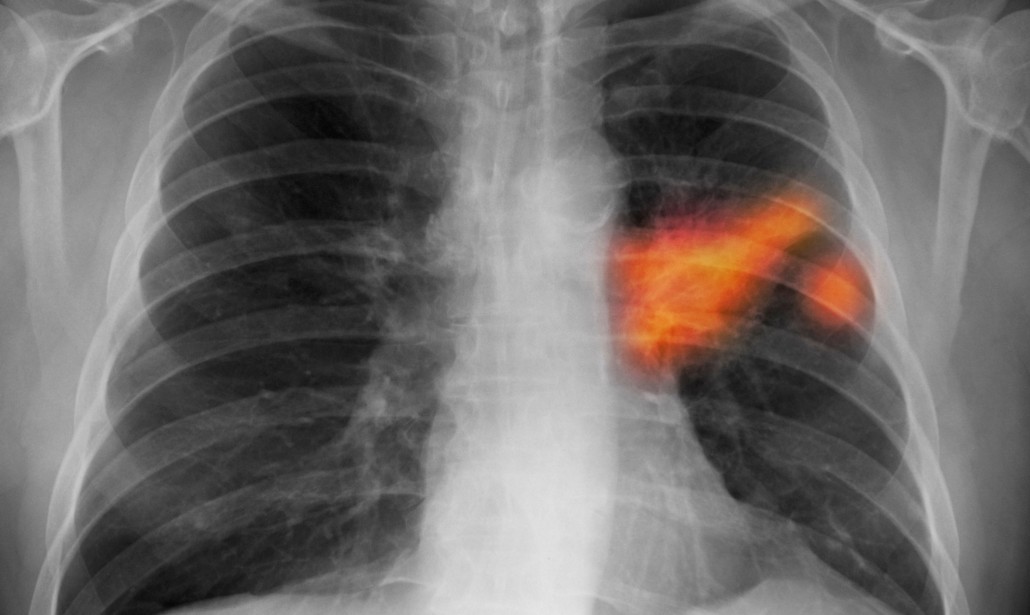

I radiologi di solito guardano attraverso centinaia di immagini 2D all’interno di una singola scansione CT e il cancro può essere minuscolo e difficile da individuare. L’approccio dei ricercatori di Google ha previsto la creazione di un modello che non solo può generare la previsione generale della malignità del cancro ai polmoni (visualizzata in maniera volumetrica 3D), ma anche identificare il sottile tessuto maligno nei polmoni (noduli polmonari). Il modello può anche prendere in considerazione le informazioni delle scansioni precedenti, utili per prevedere il rischio di cancro ai polmoni perché il tasso di crescita di noduli polmonari sospetti può essere indicativo di neoplasie.

Nella ricerca, sono stati sfruttati 45.656 casi di screening TC individuati dal set di dati dello studio National Lung Screening Trial e dalla Northwestern University. I risultati sono stat davvero impressionanti, visto che hanno rilevato un cinque percento in più di casi di cancro riducendo nel contempo gli esami falsi positivi di oltre l’11 percento rispetto alle tecniche tradizionali dei radiologi. L’approccio ha raggiunto un AUC del 94,4 percento (l’AUC è una comune metrica utilizzata nel machine learning e fornisce una misura aggregata per le prestazioni di classificazione).